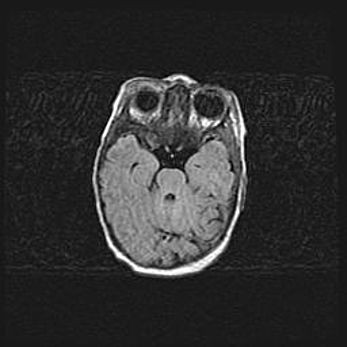

Неполная лизэнцефалия (пахигирия). Открытая гидроцефалия.

Возраст: 17 дней

Вес: 3110 г

Пол: мужской

Окружность головы: 33,5 см

Срок гестации: 35-36 недель

Лизэнцефалия—недоразвитие корковой пластинки и мозговых извилин в результате нарушения миграции нейронов коры. Поверхность мозговых полушарий гладкая. Микроскопически выявляется отсутствие нормальных слоев коры и скопление групп нейронов в подкорковом белом веществе.

Пахигирия—уменьшение числа вторичных извилин. В пораженном полушарии нервные клетки образуют толстый недифференцированный слой с неправильно расположенными нервными волокнами и группами гетеротопных клеток. Нервные клетки незрелые. Белое вещество истончено. При этом нередко аномально развит корково-спинномозговой путь.